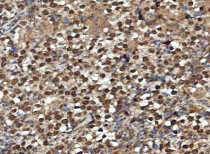

ARG44083 anti-GLI2 antibody IHC-P image

Immunohistochemistry: Human esophageal squamous carcinoma stained with ARG44083 anti-GLI2 antibody at 2 μg/ml dilution.